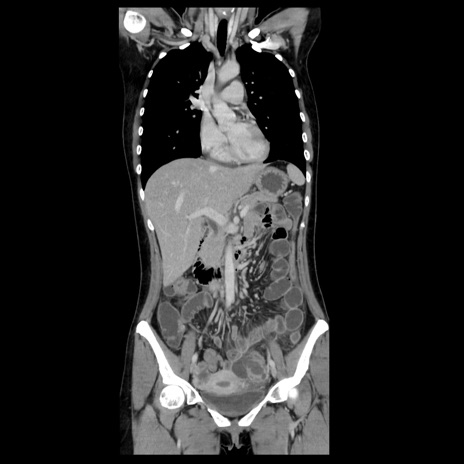

症例39(冠状断像)

【症例】40歳代女性

【主訴】上下腹部痛

【現病歴】2日目から下腹部痛あり。夜間は痛みで眠れなかった。昨日より上腹部痛と下痢が出現。臥位で痛みは軽快したため、休んでいた。本日になって臥位でも立位でも痛みが強くなってきたため救急要請。

【既往歴】子宮内膜症

【身体所見】部:平坦・軟、左上下腹部に圧痛あり、反跳痛あり。

【データ】WBC 21800、CRP 26.78

CT